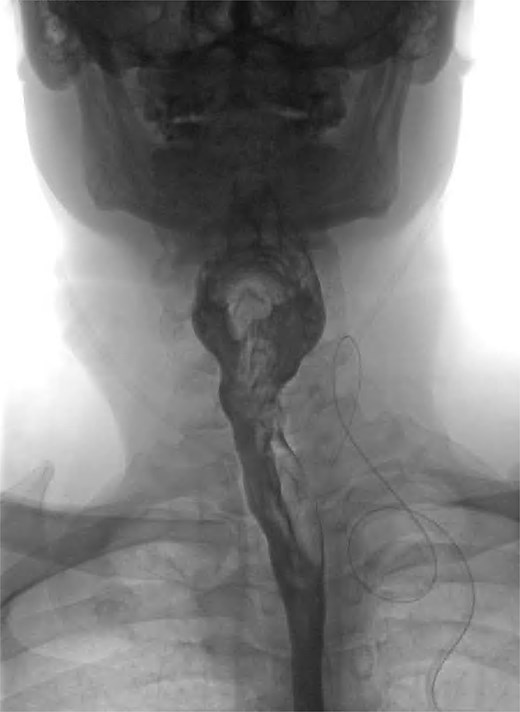

We present the case of a 57-year-old male patient who presented with dysphagia, regurgitation of undigested food, alongside a globus sensation. He had no significant medical history. He underwent a fluoroscopic swallow study, which revealed an anterolateral pharyngeal diverticulum consistent with a KJD with a neck of 5 mm and a length of 25 mm (Fig. 1). Given his symptoms, operative management was undertaken in which an incision was made along the medial border of the sternocleidomastoid. The platysma was divided, and dissection performed down to the level of the thyroid membrane with preservation of strap muscles. The left recurrent laryngeal nerve (RLN) was identified and preserved (Fig. 2). The esophageal diverticulum and sac were isolated from surrounding structures, and the neck was ligated using a 2/0 Vicryl prior to being excised. The ligation site was oversewn with 3/0 Vicryl. A drain was left, and the incision was closed in layers. Post-operatively, the patient underwent fluoroscopic swallow study, which did not show a leak or residual diverticulum, and after removal of the drain, the patient was discharged home day 1 postoperatively (Fig. 3).

Coronal view of postoperative fluoroscopic swallow study demonstrating no evidence of remnant diverticulum or leak.